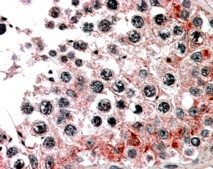

Immunohistochemistry In paraffin embedded Human Testis shows vesiculate cytoplasm staining of primary spermatocytes. Recommended concentration, 3-5µg/ml.